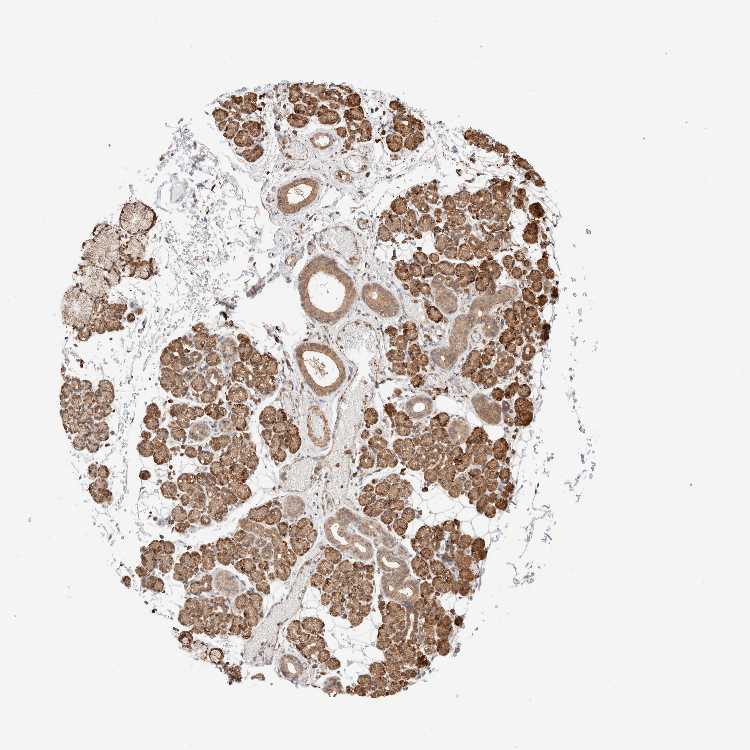

Antibody HPA021658

Glandular cells Medium